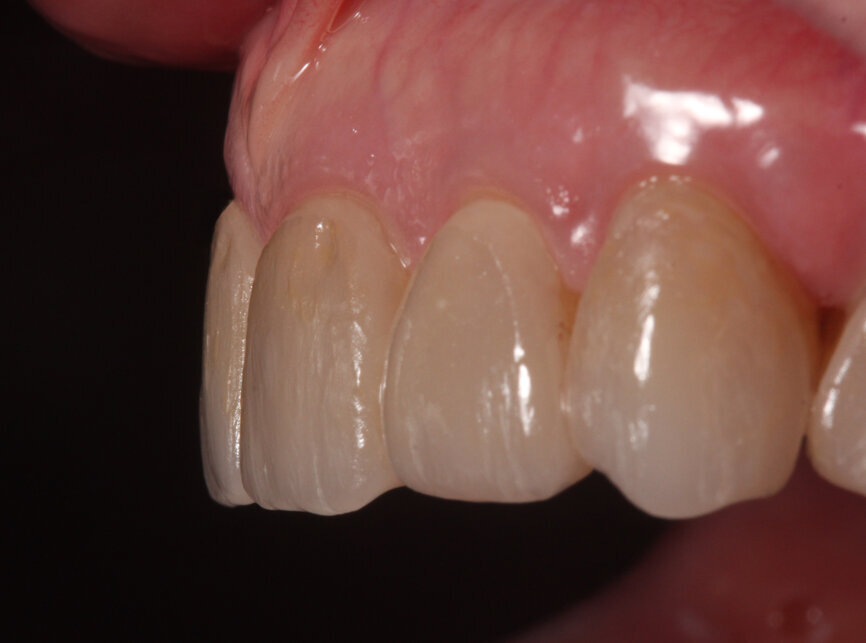

Fig. 22: Bonded veneers, lateral view.

Minimally invasive preparation (0.5–0.8 mm facial reduction and 1.5 mm incisal/occlusal reduction) was done for the labial aesthetic veneers, allowing for enamel preservation (Figs. 18 & 19). A final impression was taken and the 3D virtual design was used as the preoperative digital model, since no modifications were done intra-orally after verification. Leucite glass-ceramic blocks (IPS Empress CAD, Ivoclar Vivadent) were milled for the final veneer restorations in-house using a milling machine (PlanMill 4.0, Planmeca; Figs. 20 & 21). Final characterisation was done after glazing.

At the delivery appointment, an aesthetic try-in was done prior to bonding the restorations. The patient approved the aesthetics, marginal fit was verified, and the teeth and restorations were etched and bonded (Variolink Esthetic, Ivoclar Vivadent). The patient was extremely satisfied with the treatment outcome (Figs. 22–25). An occlusal guard was provided as part of the treatment plan. At the one-year follow-up, the patient reported no complications.